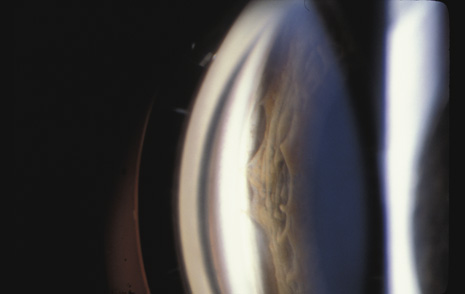

COUP AND CONTRECOUP

Courville24,25 introduced the concept of coup and contrecoup injury to explain brain damage caused by blunt trauma to the head. Coup refers to local trauma at the site of impact. Contrecoup refers to injuries at the opposite side of the skull caused by shock waves that traverse the brain. Foci of brain damage are found along the path of the shock waves, especially at interfaces of tissues of different density. The greatest difference in density is between the brain and the skull, and it is here that the most severe damage occurs. Wolter later used these concepts to explain eye injuries.26 Examples of coup injuries are corneal abrasions, subconjunctival hemorrhages, choroidal hemorrhages, and retinal necrosis (Fig. 1). The best example of a contrecoup injury is commotio retinae (Fig. 2). These injuries are discussed later in this chapter.

Fig. 1. A: Coup injury. At the site of impact of a stick, subretinal and vitreous hemorrhage are present. B: Three months later, most of the hemorrhage has cleared, revealing choroidal and pigment epithelial necrosis.

Fig. 2. Contrecoup injury. When a blunt object strikes the eye, shock waves traverse the eye to strike the posterior pole.